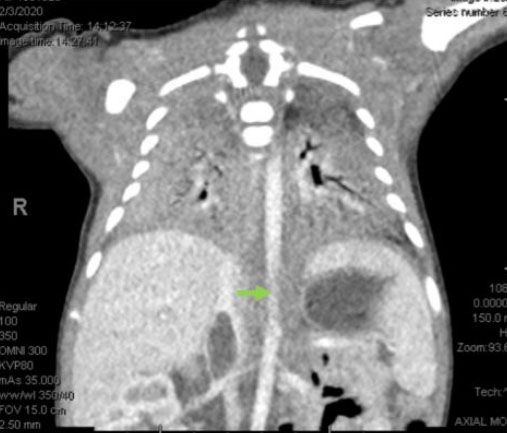

On post-op day 1, the mother restarted her LMWH and was recovering well. On day 1 of life, the neonate underwent an ultrasound showing a similar appearing focal non-occlusive clot. On day 2 of life, there were no intracardiac clots visualized on the echocardiogram and PGE was stopped. On post-op day 3, the mother was discharged home. On day 3 of life, a computed tomography (CT) angiograph was performed and it was determined that the clot seemed to be recently formed, was deforming the IVC, and was not well attached to the vessel wall because there was blood flow around it, thus raising concern for embolization risk (Figure 4).

Figure 4: Computed tomography angiograph of neonate with inferior vena cava thrombosis at green arrow.